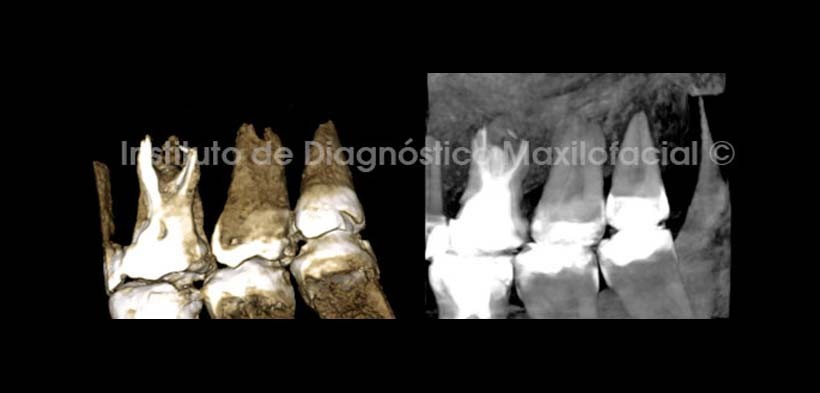

En las reconstrucciones tridimensionales (Fig. 6) se observan los signos tomográficos descritos en las imágenes anteriores de forma mas ilustrativa.